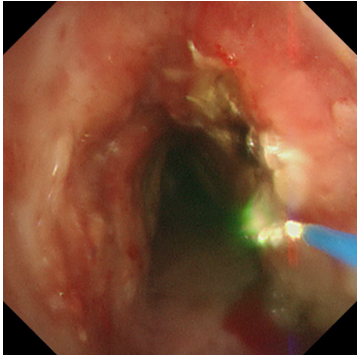

患者王先生(化名),20多年前因喉癌接受了喉切开手术,长期留置气管套管。一周前,他再次感受到熟悉的窒息感——呼吸困难加剧,喉间痰鸣,却有痰咳不出,每一次吸气都异常费力,家人紧急将他送至瑞康医院救治。经检查,王先生的气道出现了严重的增生性狭窄。新生的肉芽组织像藤蔓一样在主气道内生长,使得原本就不宽敞的呼吸道变得更加狭窄,最严重处堵塞程度超过50%。这不仅是导致他呼吸困难的直接原因,也使得分泌物无法排出,易引发肺部感染和呼吸衰竭,情况万分危急。

激光灼蚀,精准“开路”:在气管镜引导下,首先利用高频激光对堵塞气道的增生组织进行精准、迅速地汽化切割。激光如同一位技艺高超的“雕刻师”,快速清除掉大部分梗阻物,为后续治疗打开一个通畅的“窗口”,迅速缓解患者的窒息风险。